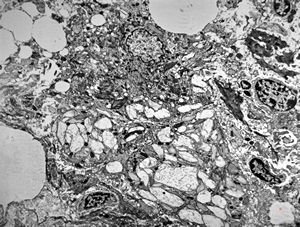

Whipple disease